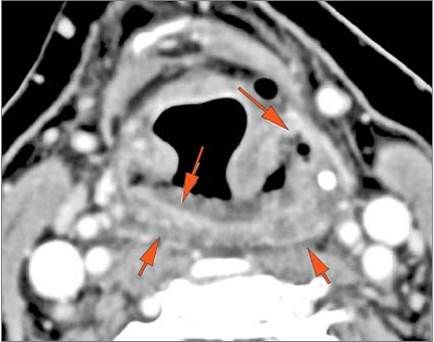

9 month old male presenting to the emergency room with poor feeding, fever, respiratory distress and possible retropharyngeal abscess or suppurative retropharyngeal adenitis.Exam

There is edema within the adjacent deep neck, retropharyngeal and/or prevertebral spaces |

No | NA |

There is edema/abscess within in the prevertebral or paravertebral spaces. |

Yes | NA |

| Upper Lung Zones and Mediastinum | Correct Answer | Your Answer |

The upper lung zones and mediastinum visualized are abnormal. |

Pharyngitis with suppurative retropharyngeal adenitis.